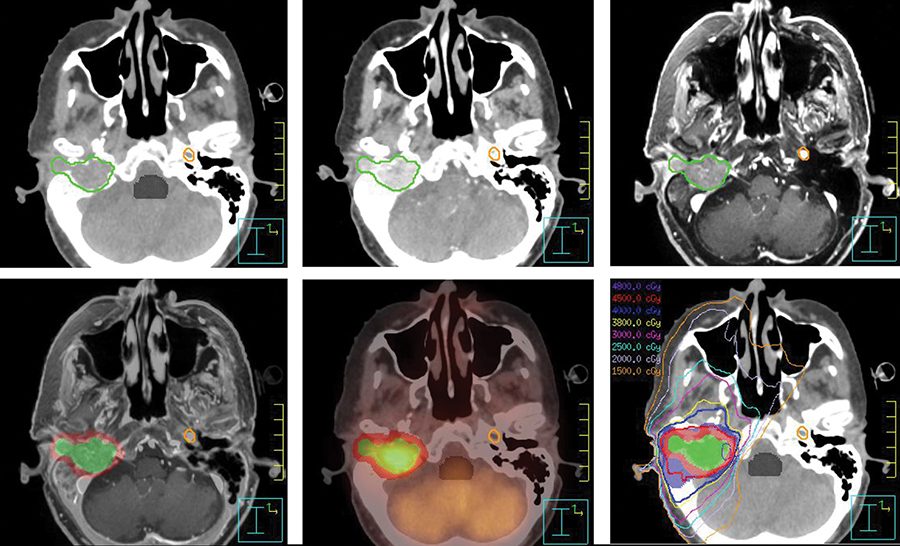

Brain cancer skull. Brain metastasis in the right cerebral hemisphere from lung cancer shown on magnetic resonance imaging. The bones of the skull that form the bottom of the head and. A brain tumor is a collection or mass of abnormal cells in your brain.

To the brain and skull. Any growth inside such a restricted. Brain tumors can begin in your brain primary brain tumors or cancer can begin in other parts of your body and spread to your brain secondary or metastatic.

To your specific skull base cancer. Learn about our experience with brain and skull base tumors including research clinical trials minimally invasive keyhole surgery and treatment options. Skull base tumors are not a particular type of brain tumor but those that grow in a particular location.

Treatment of brain tumour is a delicate process.